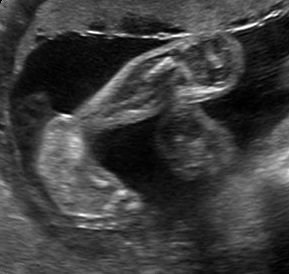

Sonoanatomie, Biometrie, Hinweiszeichen & Diagnose von Entwicklungsstörungen, Kasuistiken, ausreichend Zeit für Diskussionen, Fallbeispiele aus der Praxis (Quiz)